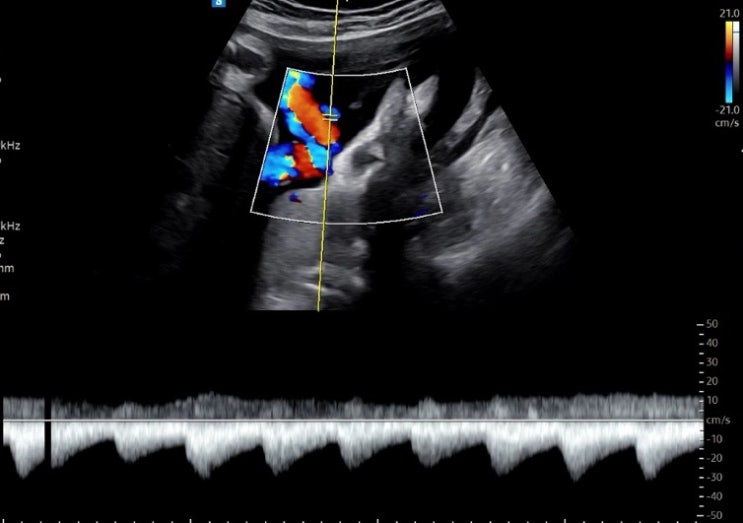

[임신 32주차] 동탄제일병원 첫 태동검사(but 재검..) 호캉스 후 피비침??!!